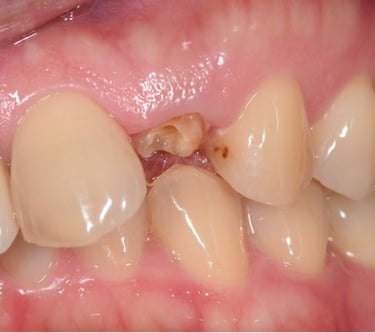

Pérdida de un diente único

La pérdida de un diente único es cuando un solo diente se ha caído o ha sido extraído, y se necesita un implante para reemplazarlo.

Los pacientes pueden notar un espacio donde solía estar el diente. Esta condición puede afectar la estética y la función masticatoria.

El tratamiento incluye la colocación de un implante dental para restaurar el diente perdido.